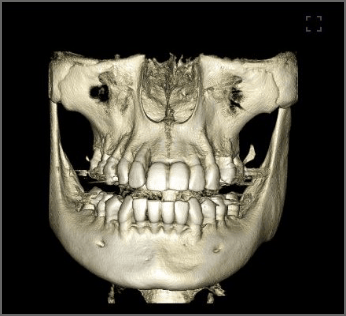

70μm(Voxel Size)高精細モード搭載

End、根尖、破析、分岐部病変など精細読影をサポートします。

CT撮影時、Free FOVで撮影に必要な領域を絞り込み、

的確に高解像度70μmの世界トップレベルのCT画像を再現します。-

根管END

-

前歯クラック

(亀裂) -

埋伏歯

過剰歯